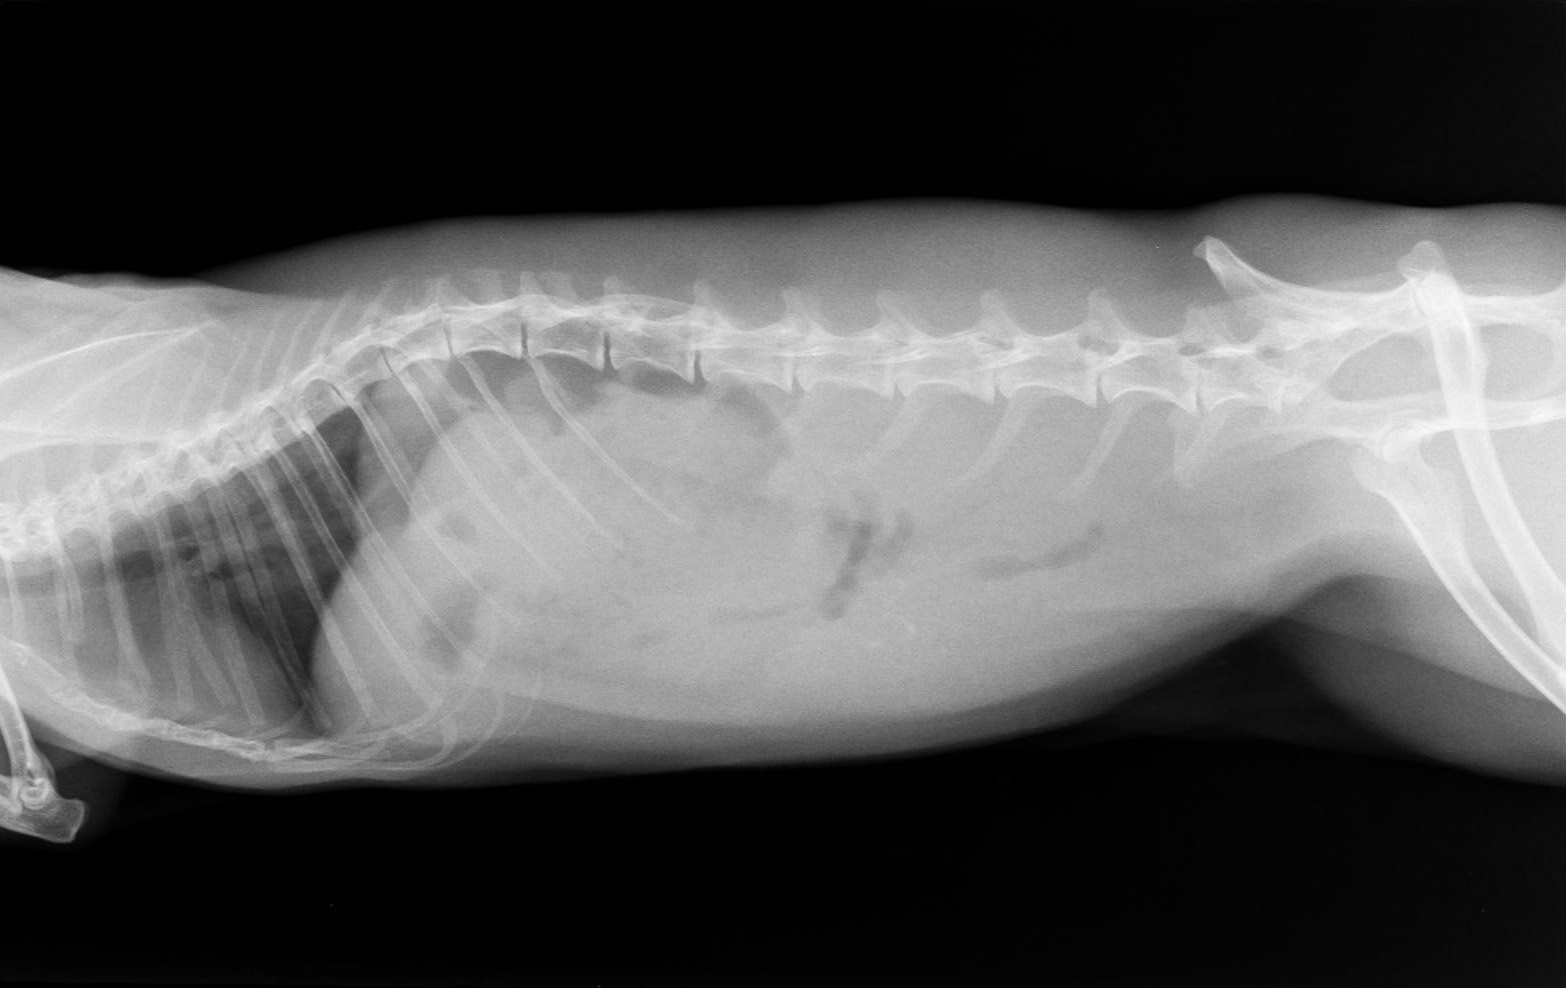

触診で胃の大きさをチェック、レントゲン上で食事していないのに胃内に異物が入っていることを確認する

半日以上食べていないのに、胃内にものが確認できる場合は毛球症の可能性が高い。

食欲不振のウサギ、食べていないのに胃内に内容物がかなり入っている。盲腸部位にはガスが出ていないので比較的短期間で悪化したことを示している。